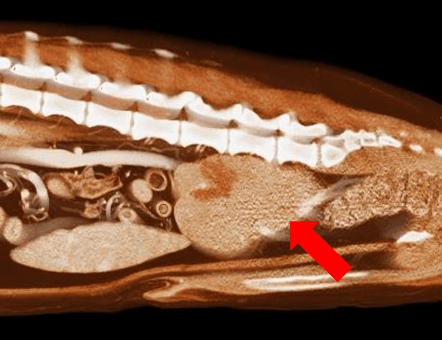

【実施症例】肝臓腫瘍に対する動注療法

柴犬、12歳、雄。

肝臓内側左葉に発生した巨大肝臓腫瘍。高齢で手術リスクが高いため、肝臓腫瘍に対して TACE(肝動注化学塞栓療法)を実施した。 実施から1ヵ月後のエコー検査で、腫瘍の若干の縮小と内部の壊死が認められた。

肝臓腫瘍の3D・CT画像